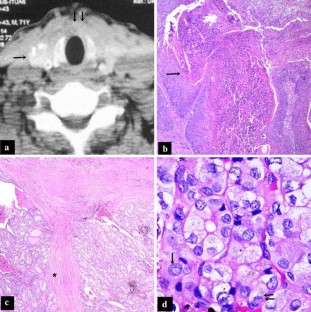

The occurrences of multiple primary malignant tumours in the head and neck region are reported as simultaneous, synchronous, or metachronous based on their chronology of presentation. Lymphoid malignancies presenting in association with squamous cell carcinoma in the head and neck region are extremely rare. We report a case of a 71 year old male patient with simultaneous triple primary malignancies of different histologic origin, involving larynx (squamous cell carcinoma), thyroid (papillary thyroid carcinoma) and lymph nodes (non-Hodgkin’s lymphoma).

Fig. 1

Fig. 2